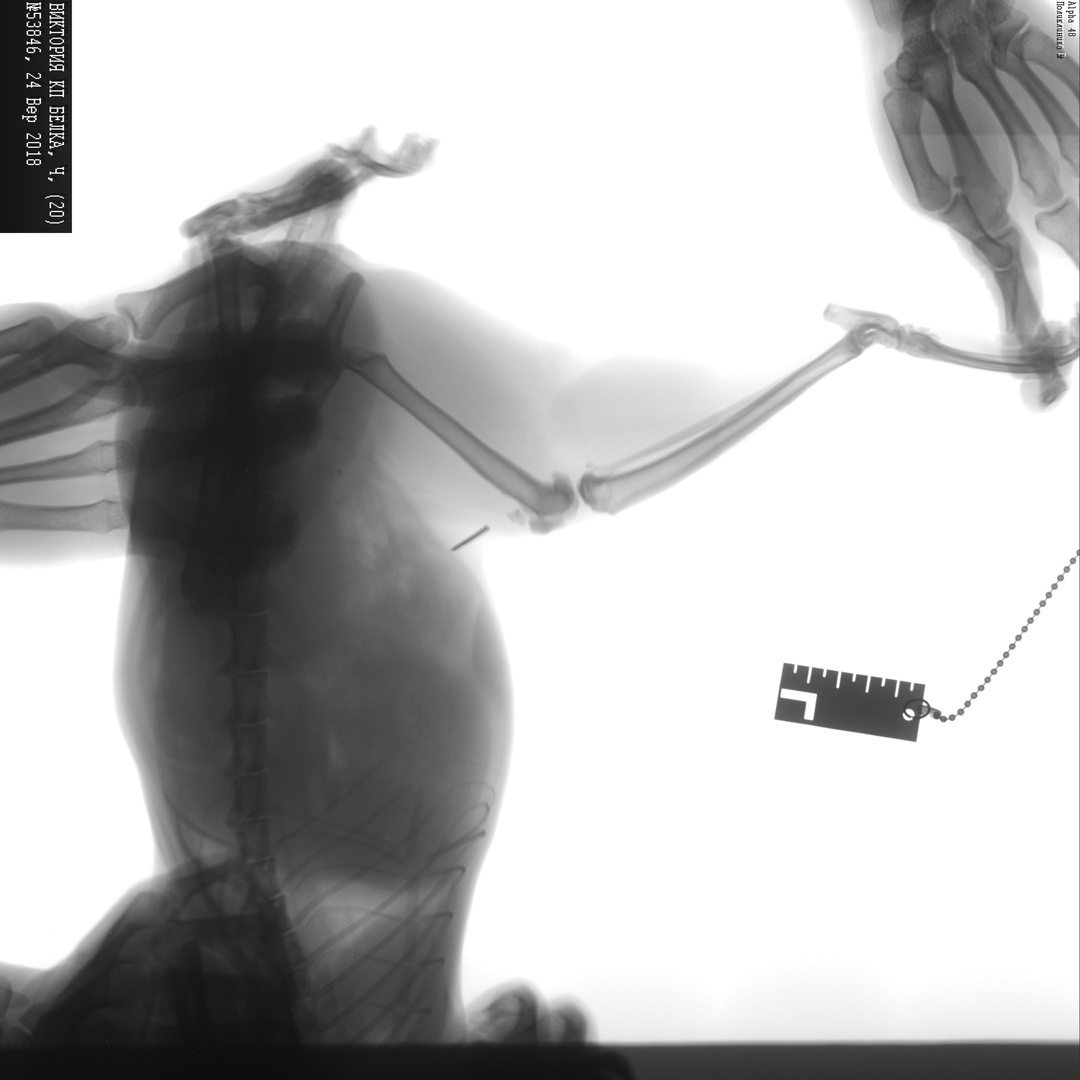

Белке установили 2 спицы на сломанный внутрисуставной перелом задней левой ноги.

Сегодня удалось сделать повторный снимок. Одна спица, которую оставили, ( вторую извлекли еще в 2017 г после сращения сустава), начала путешествовать. Необходимо ее удалять. Снимок третий - до операции, второй и первый - контроль сегодня.